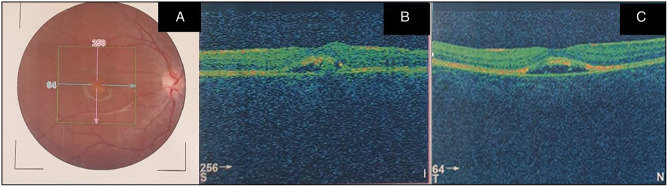

An 11-year-old boy presented to the retina outpatient clinic with a -5-year history of poor vision in the left eye. The best corrected visual acuity at presentation was 6/5 and 6/36, respectively, in the right and left eyes. Ocular examination revealed normal anterior segments in both eyes. Binocular indirect ophthalmoscopy of the right eye revealed a pink disc with a cup disc ratio (CDR) of 0.3, normal vessels while the macula had a yellowish lesion with a scrambled egg appearance and surrounding dome-shaped subretinal fluid with a flat retina and no treatable peripheral retinal lesions. The left eye had a pink disc with CDR O.3, normal vessels with a hyperpigmented lesion at the macula surrounded by a small cuff of subretinal fluid with a flat retina and no treatable peripheral retinal lesions. Optical coherence tomography scan revealed subretinal fluid in both eyes with an active choroidal neovascular membrane in the left eye. He was advised on the need for left intravitreal anti-vascular endothelial growth factor injections.